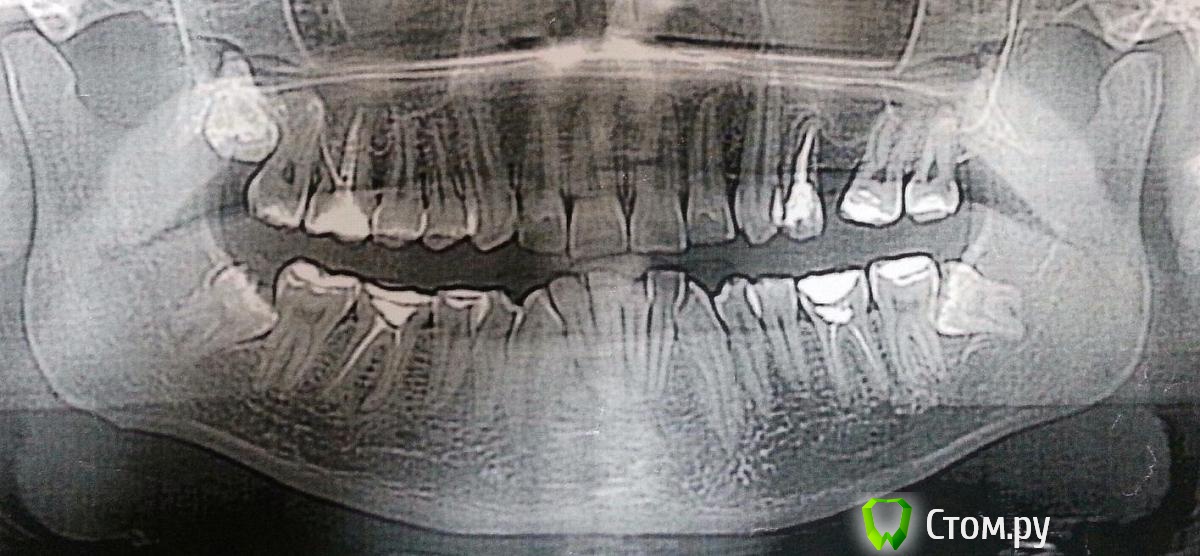

minchia Опубликовано 14 ноября, 2013 Поделиться Опубликовано 14 ноября, 2013 Здравствуйте, уважаемые стоматологи! Обращаюсь к вам за советом. У меня в нижней челюсти очень кривые зубы, кроме того, у меня в верхней челюсти слева удалены два зуба, изза чего съехала серединная линия. Решил ставить брекеты, и сходил на прием к ортодонту, он сделал снимок (приложение), и сказал нужно удалять три зуба мудрости для высвобождения места. Правильно ли это? Кроме того он предлагает поставить распорку между зубами, где есть брешь для того, чтобы открыть место для двух имплантов.Есть ли альтернативы этому лечению, можно ли избежать удалений?Какой тип брекетов подойдет лучше всего? Ортодонт настаивал на системе Деймона, оправданно ли это?Спасибо большое за помощь! Ссылка на комментарий

Ayrat_zub Опубликовано 14 ноября, 2013 Поделиться Опубликовано 14 ноября, 2013 Здравствуйте, уважаемые стоматологи! Обращаюсь к вам за советом. У меня в нижней челюсти очень кривые зубы, кроме того, у меня в верхней челюсти слева удалены два зуба, изза чего съехала серединная линия. Решил ставить брекеты, и сходил на прием к ортодонту, он сделал снимок (приложение), и сказал нужно удалять три зуба мудрости для высвобождения места. Правильно ли это? Кроме того он предлагает поставить распорку между зубами, где есть брешь для того, чтобы открыть место для двух имплантов.Есть ли альтернативы этому лечению, можно ли избежать удалений?Какой тип брекетов подойдет лучше всего? Ортодонт настаивал на системе Деймона, оправданно ли это?Спасибо большое за помощь! да, зубы мудрости удалять, еще следует заняться зубами 36, 46, с каналами там дело нечисто) Ссылка на комментарий

minchia Опубликовано 11 января, 2014 Автор Поделиться Опубликовано 11 января, 2014 Итак, пришло время ставить брекеты на верхнюю челюсть. На нижнюю поставили две недели назад. Три недели назад были удалены три зуба мудрости. Вопрос: ортодонт предложил два варианта лечения - закрыть трему в верхней челюсти слева передвижением вперед 7 и 8 зубов. Тогда установка импланта не потребуется (вместо удаленного 6-го зуба), второй вариант - раздвигать зубы для высвобождения места под имплант. Какой вариант предпочтительнее? Насколько реально передвинуть 7 и 8 зубы с корнями вперед почти на 7-8 мм? Сколько это займет времени? Каковы шансы на успех? Ссылка на комментарий